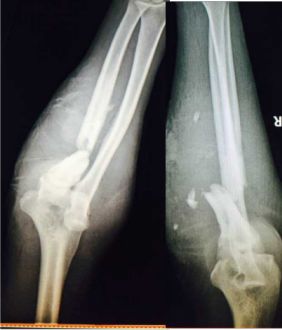

胫骨远端简单骨折选用钢板固定没有实现坚强固定,钢板承受应力,孔处应力集中断裂

下一例:是胫骨骨折局部钢丝螺钉内固定太多干扰骨愈合,骨不连接钢板迟早断裂。

开放骨折,软组织损伤严重,骨不连接导致钢板断裂。应当在伤口愈合后及时干预植骨